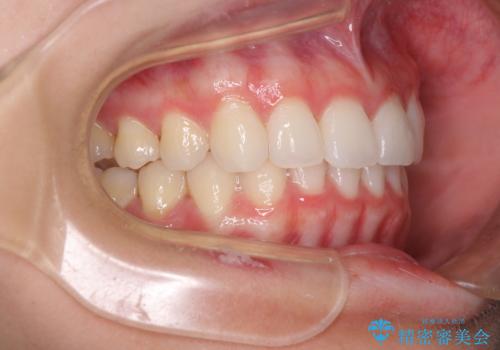

- 前歯2本が飛び出してることを気にして来院された患者様です。

全体的に黄ばんだ歯の色も気になるとのことで、マウスピース矯正により飛び出した前歯を治しつつ、ホームホワイトニングを併用して黄ばみを解消していくこととしました。

歯と歯の間を削ることで、飛び出した前歯が引っ込み、スッキリとした口元となりました。

歯の黄ばみも改善され、明るい歯並びとなりました。